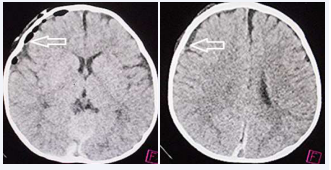

The patient was brought to a nearby hospital where signs of altered consciousness status was confirmed, prompting to undergo head CT (Figure 1).

Figure 1 Computed tomography on arrival. Left (Coronal View), Right (Axial View). Acute subdural hematoma with mixed density on the right side (arrows). Large sylvian fissure on the left side (asterisk), contralateral to the subdural hematoma

Figure 1: Computed tomography on arrival. Left (Coronal View), Right (Axial View). Acute subdural hematoma with mixed density on the right side (arrows).

Large sylvian fissure on the left side (asterisk), contralateral to the subdural hematoma

Based on the CT findings showing ASDH on the right side associated with LSF on the left side, the neurosurgen decided to undergo emergency surgery.